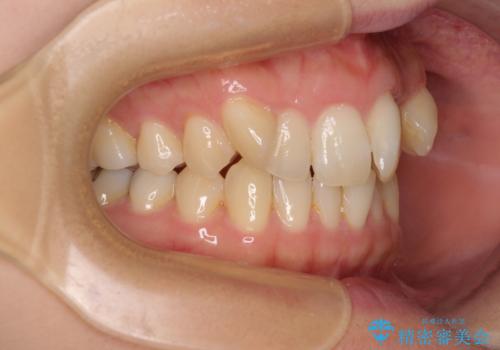

- 目立つ八重歯を気にして来院された患者様です。

下顎歯列の叢生は軽度であることと、口元の突出感が全くなかったことから、八重歯解消のために上顎左右第一小臼歯を抜歯し、ワイヤー装置にて矯正治療を行うこととしました。